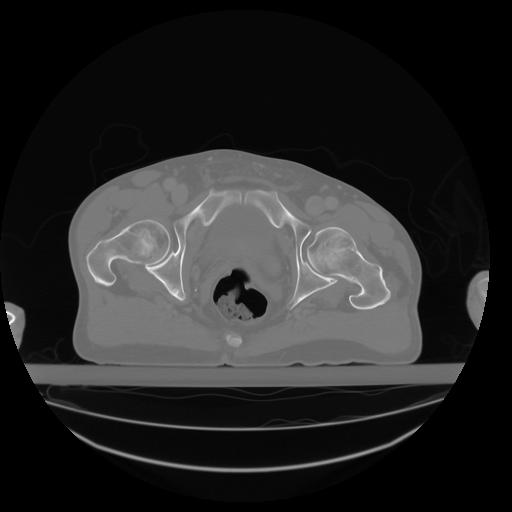

27 CUERPO,CE,Axial,3.0,CUERPO,,